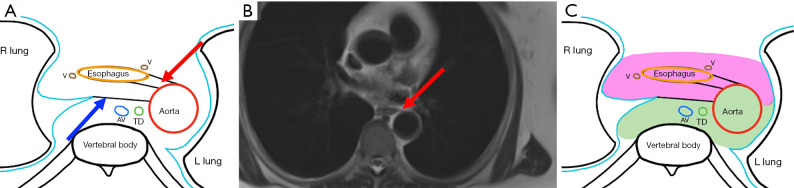

While it is not uncommon to see central mediastinal diseases on cross-sectional imaging, it is important to understand the pathway influencing the spread of disease at a radiological point of view. The advent of minimally invasive thoracic surgeries has led to the discovery of unknown tissue planes in the mediastinum such as the aorto-esophageal (AE) and aorto-pleural (AP) ligaments. In particular, the AE ligament is a portion of the mediastinal visceral fascia, which courses from the anterior aspect of the aorta to the left lateral aspect of the esophagus. It can be visualized on computed tomography (CT) and magnetic resonance imaging (MRI); it courses longitudinally from the level of the aortic arch to the level of the diaphragm. This recently discovered unknown anatomy aids us in understanding the possible pathway of spread of disease processes such as air, fluid, and soft tissue in the mediastinum. In addition, it acts as an important anatomical landmark in determining the location of lymph node metastases from esophageal cancer, which will further influence the possibility of thoracic duct resection/sparing. Finally, the AE ligament can be utilized in the preoperative planning of minimally invasive thoracic surgeries and can potentially be used as a dissection plane during esophagectomies.